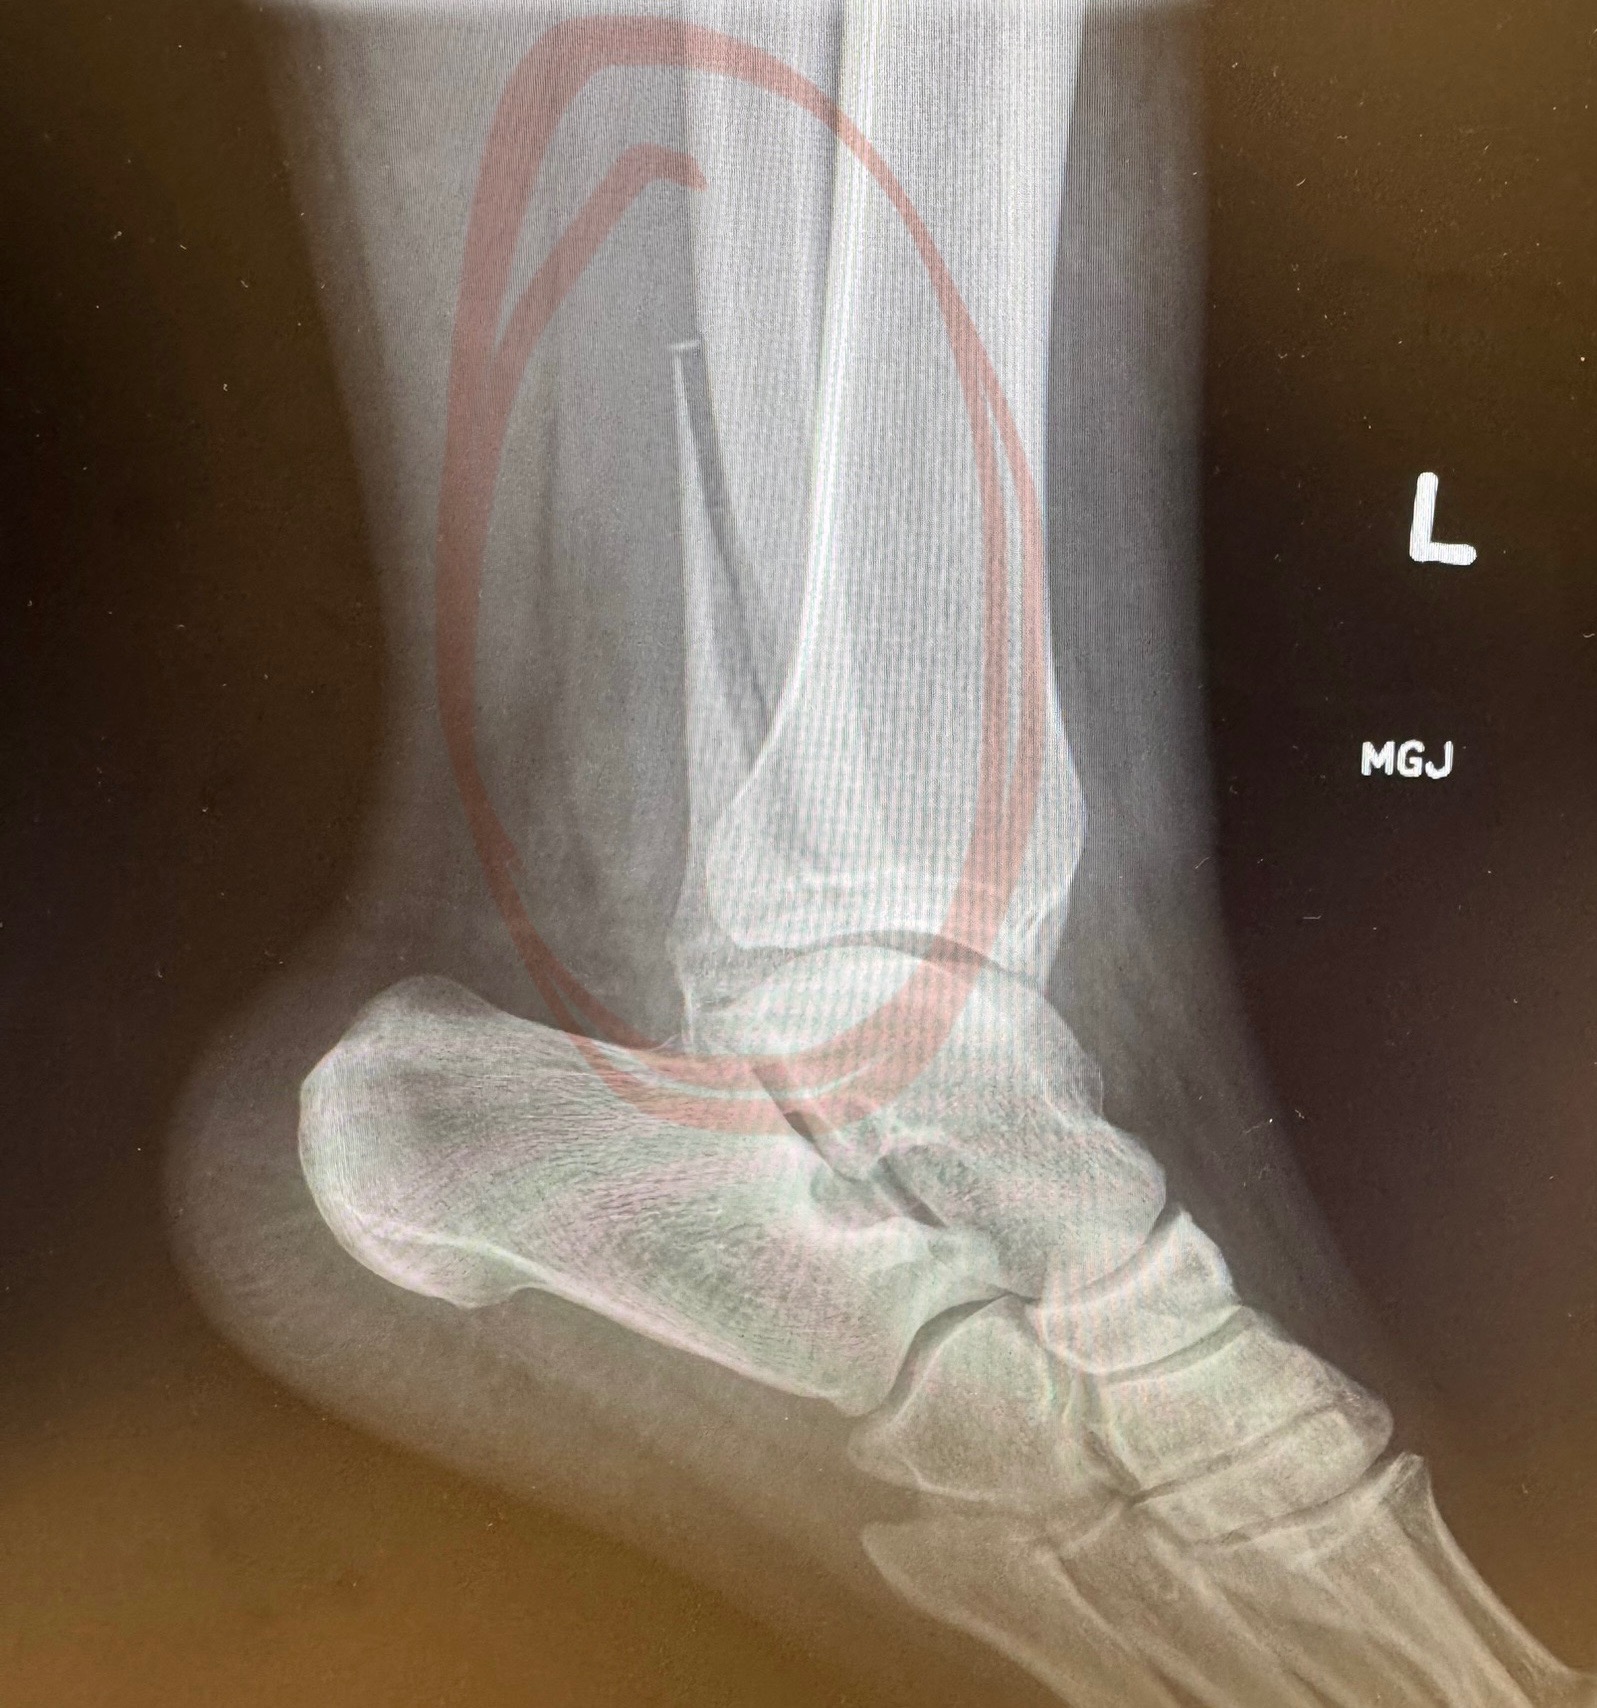

I recently experienced a slip and fall accident during my vacation in Washington D.C., during Memorial Weekend which resulted in a broken fibula of my left ankle and I had to be rushed to the emergency room on Monday, May 26. The injury was so severe that I was refferred to an Ortopedic surgeon to discuss surgery which required me to receive a metal plate and screws or risk having complications in the long run which could include amputation. I completed the surgery on Tuesday, June 17 successfully and was given instructions that I cannot walk on it for at least 6-8 weeks before starting physical therapy which would keep me out of work for over 2-3 months.